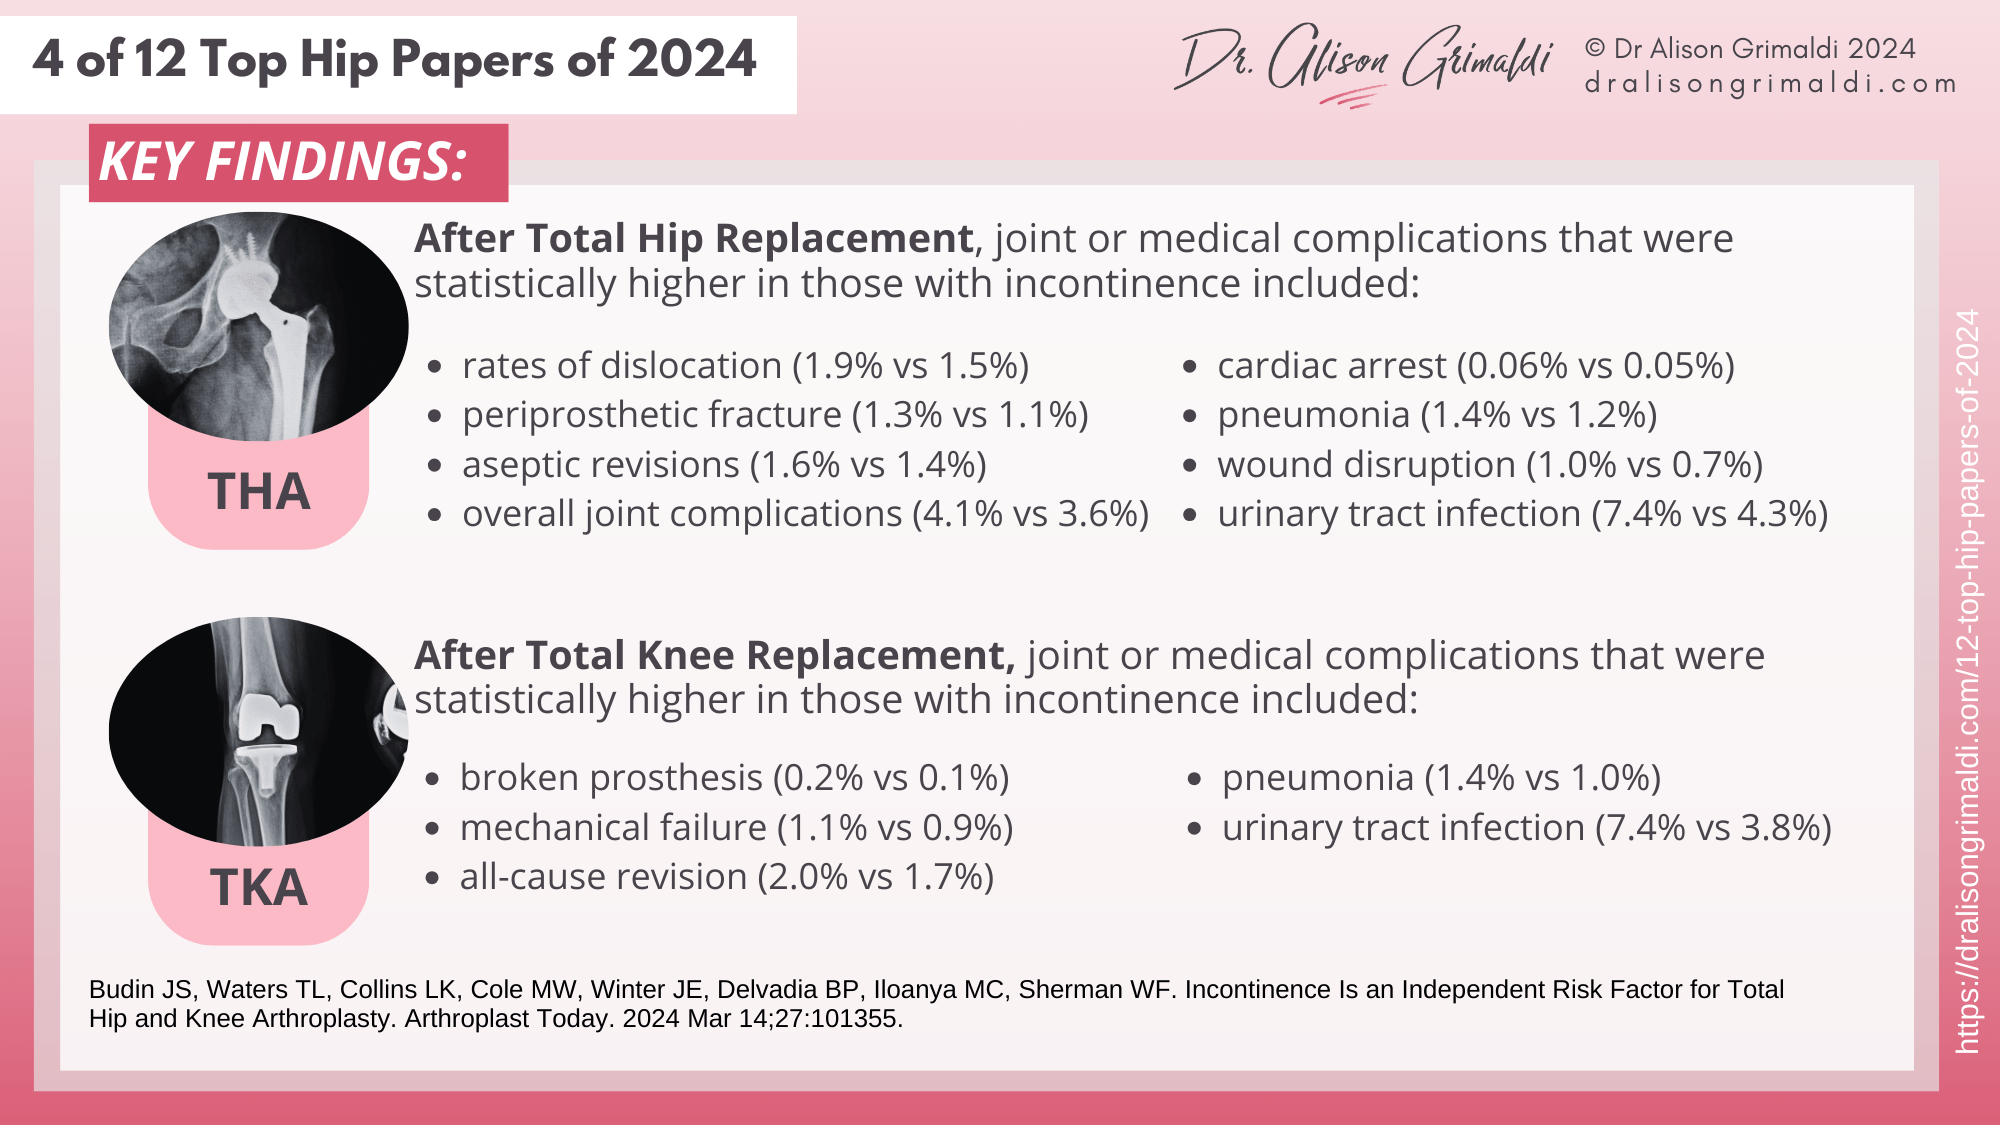

Key Findings:

- Those with urinary incontinence had statistically higher rates of medical and joint complications following total hip arthroplasty and total knee arthroplasty. See the details in the infographic below.

- Incontinence is more common in those with medical conditions such as Multiple Sclerosis and Parkinson’s disease but remains an independent risk factor for both medical and joint complications following total hip and knee replacements.

Those with incontinence had higher risks of joint and medical complications, particularly in females after total hip replacement. While chronic disease status is linked - incontinence is more prevalent is those with Multiple Sclerosis and Parkinson's disease - incontinence remains an independent predictor of increased post-operative complications. Pelvic floor and hip muscle function are both known to be poorer in those with incontinence, and continence and muscle function may both be influenced by hip arthroplasty.